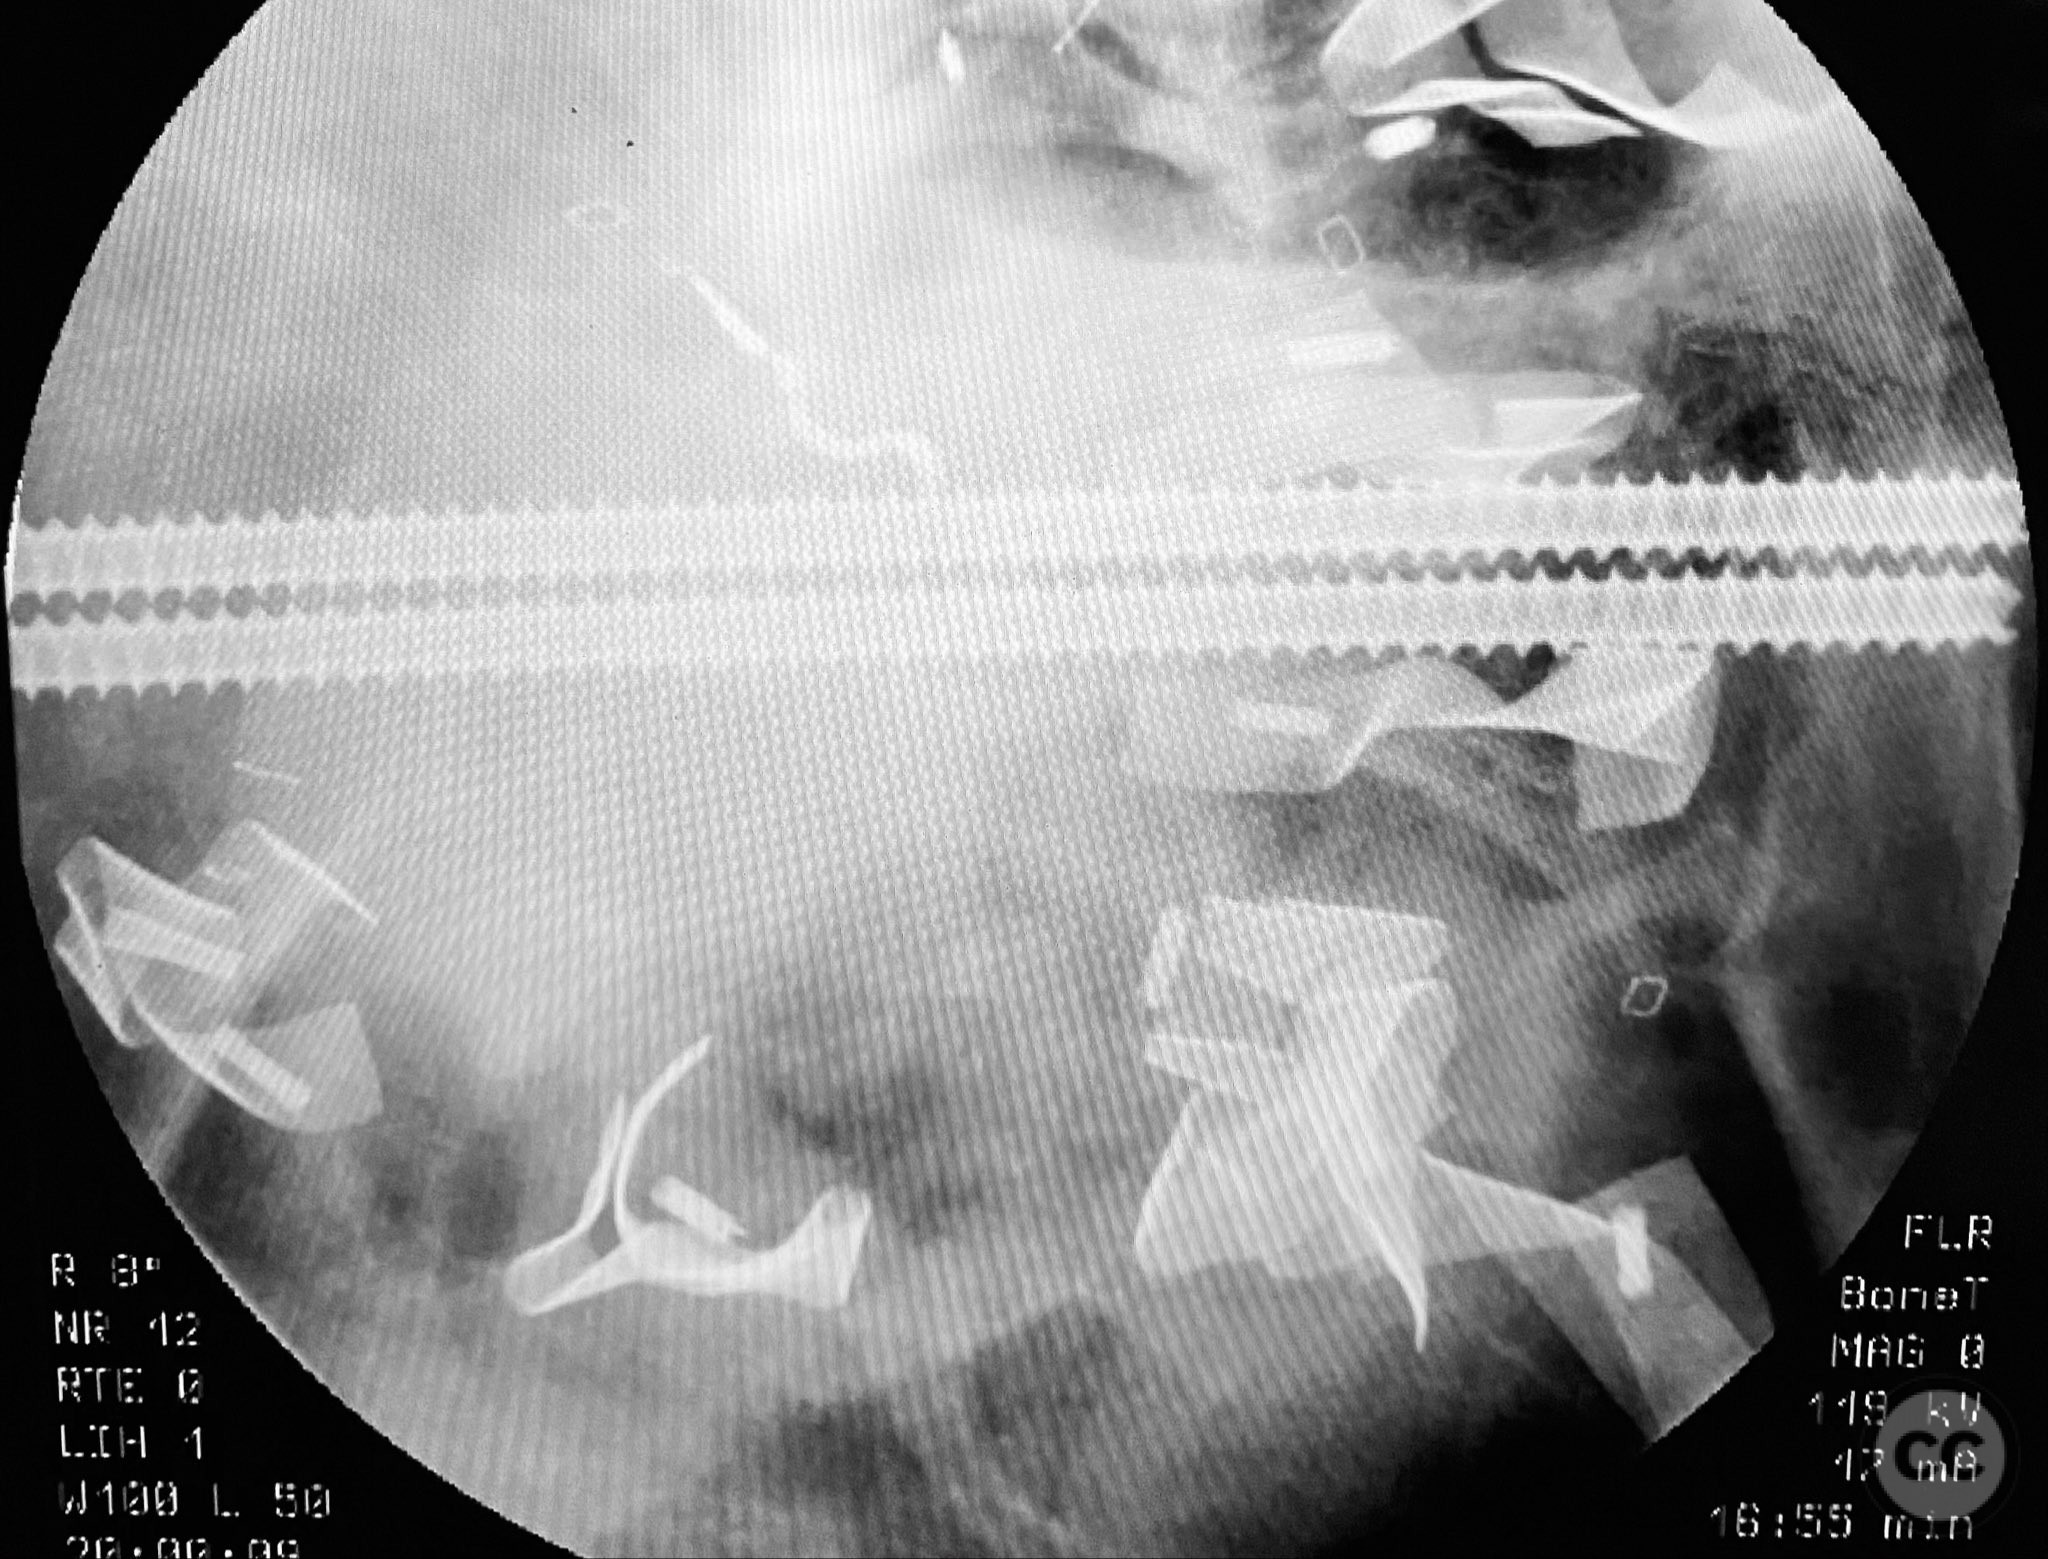

Planning remarks:  The preoperative plan included early closed reduction maneuvers under fluoroscopic guidance, percutaneous stabilization of the pelvic ring with cannulated screws, and intramedullary nailing of the proximal femur. The anatomical approach for pelvic fixation was percutaneous iliosacral screw placement; for the femur, a standard antegrade intramedullary nailing technique was planned.

Patient positioning:  The patient was positioned supine on a radiolucent operating table to facilitate access to the pelvis and proximal femur, with the affected limb in traction via a distal femoral pin.

Anatomical surgical approach:  Percutaneous iliosacral screw fixation was performed through small lateral gluteal incisions, with blunt dissection to the outer table of the os ilium. Under fluoroscopic guidance, guidewires were advanced across the sacroiliac joint into the S1 body, followed by cannulated screw insertion. For the proximal femur, a longitudinal incision was made proximal to the greater trochanter, splitting the fascia lata and gluteus medius fibers to access the piriformis fossa. A guidewire was inserted into the medullary canal, followed by sequential reaming and insertion of an intramedullary nail.

Intraoperative imaging was challenging due to osteopenic bone, fracture comminution, and interference from abdominal packing. Accurate identification of safe osseous corridors for iliosacral screw placement required multiple fluoroscopic projections and careful attention to pelvic landmarks. Bone quality necessitated cautious screw advancement to avoid iatrogenic cortical breach. After pelvic fixation, intramedullary nailing of the proximal femur proceeded without complication. Abdominal packing was removed and laparotomy wound closed after skeletal stabilization. Early mechanical stabilization of both pelvic and femoral injuries was prioritized to optimize survivability in this multiply injured elderly patient.